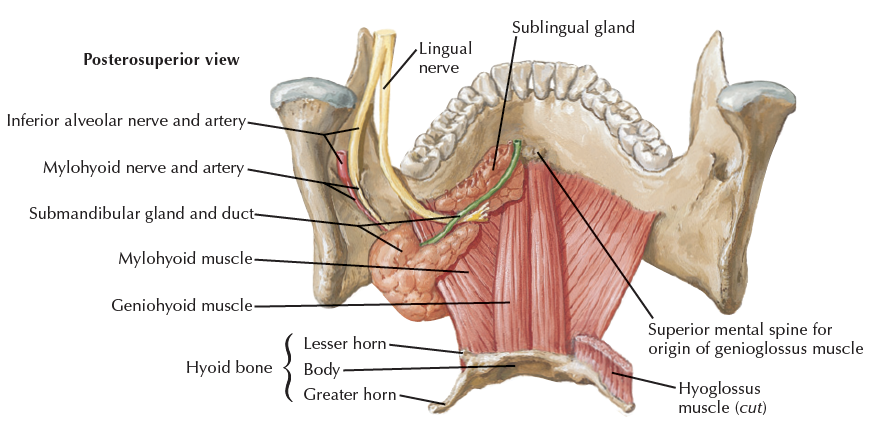

Hyoglossus m. 外側

- Lingual n.

- Hypoglossal n.

- Submandibular duct

Lingual a.

Genioglossus m., Hyoglossus m.之間

- Deep lingual a.

- Sublingual a.

- 會合 Submental a. (Facial a. 分支)

- Sublingual g. Mylohyoid line Submandibular g.

舌骨上

| Mylohyoid | CN V3 |

| Digastric | Ant. belly: CN V3 Post. belly: CN VII |